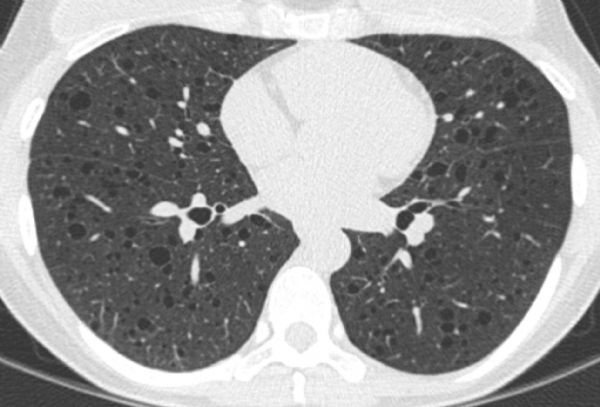

Jay H. Ryu, Xinlun Tian, Misbah Baqir, Kaifeng Xu

Diffuse cystic lung diseases are uncommon but can present a diagnostic challenge because increasing number of diseases have been associated with this presentation. Cyst in the lung is defined as a round parenchymal lucency with a well-defined thin wall (<2 mm thickness). Focal or multifocal cystic lesions include blebs, bullae, pneumatoceles, congenital cystic lesions, traumatic lesions, and several infectious processes such as coccidioidomycosis, Pneumocystis jiroveci pneumonia, and hydatid disease. “Diffuse” distribution in the lung implies involvement of all lobes. Diffuse lung involvement with cystic lesions can be seen in pulmonary lymphangioleiomyomatosis, pulmonary Langerhans’ cell histiocytosis, lymphoid interstitial pneumonia, Birt-Hogg-Dubé syndrome, amyloidosis, light chain deposition disease, honeycomb lung associated with advanced fibrosis, and several other rare causes including metastatic disease. High-resolution computed tomography of the chest helps define morphologic features of the lung lesions as well as their distribution and associated features such as intrathoracic lymphadenopathy. Correlating the tempo of the disease process and clinical context with chest imaging findings serve as important clues to defining the underlying nature of the cystic lung disease and guide diagnostic evaluation as well as management.